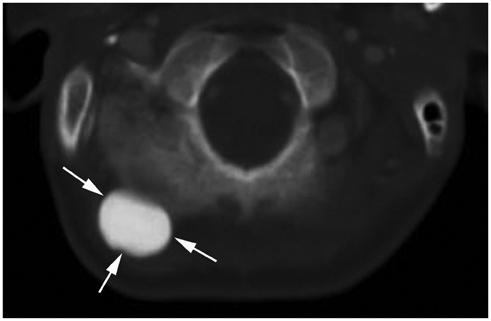

Systematic Approach of Sclerotic Bone Lesions Basis on Imaging Findings

- Sclerotic bone lesions are common, but there are diverse groups of tumors and non-tumorous lesions. Although plain radiograph and computed tomography can reveal important characteristics of these lesions, diagnosis is often challenging for radiologists. A systematic approach and familiarity with the imaging features of various sclerotic bone lesions may be greatly helpful for eliminating in the differential diagnosis. This review describes the systematic approach to diagnosing sclerotic bone lesions based on imaging findings.